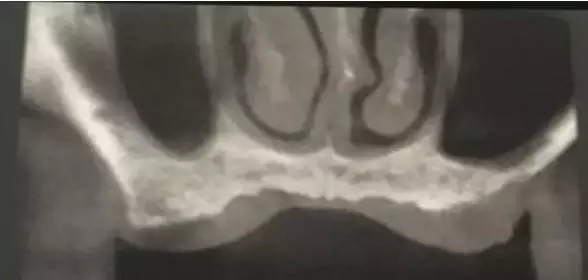

患者50歲,男性,身體健康。左上6,7缺失,骨高度2mm。

術前口內照和CT片。

1.webp.jpg

2.webp.jpg